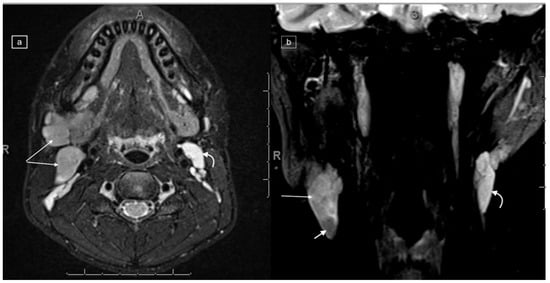

Figure 4.

Images demonstrating technical reasons for lower T2 signal of lymphadenopathy. MRI of the cervical region in a 12-year-old male with a histologic diagnosis of nodular sclerosing Hodgkin lymphoma. The right lower cervical lymphadenopathy (arrows) demonstrates low signal on T2 (a) and higher signal on STIR (b), with only mild enhancement on post-gadolinium T1-weighted imaging (c).